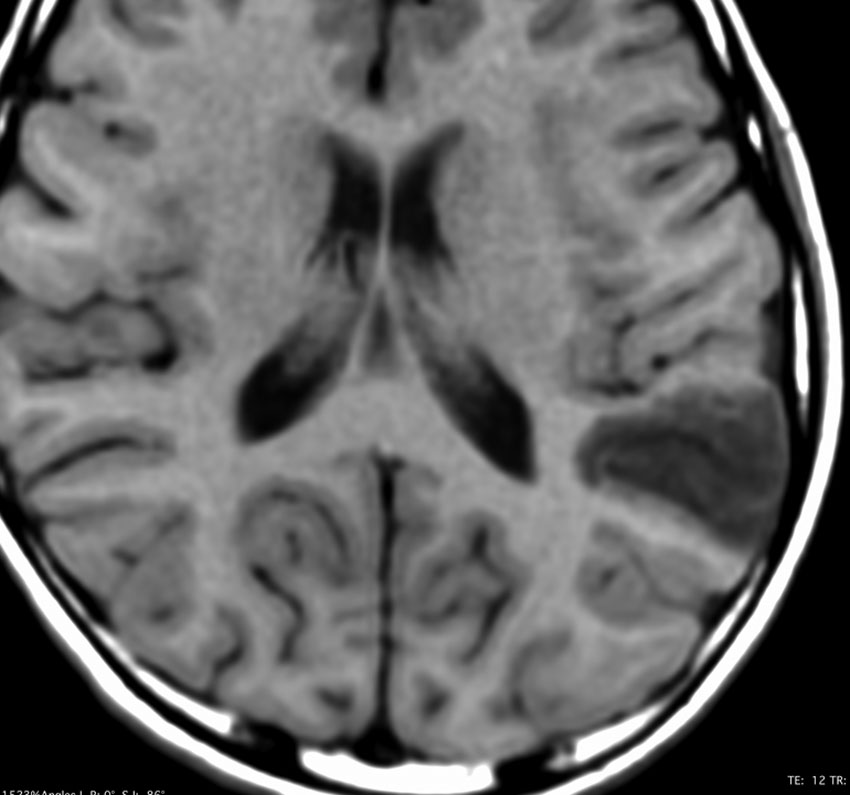

3歳で最初のてんかんらしいと言われる発作があり,その後は発作は見えず自動症と診断され徐々に学習能力の低下が認められ,7歳の時に外来を訪れました。週に3回くらい腹痛や嘔気があってすぐに眠くなってしまう。耳鳴がすごくてしばらく何も聞こえなくなってしまう,話も理解できなくなるなど,側頭葉てんかんの特徴をたくさんエピソードとして持っていましたが,症候性てんかんとは診断されませでした。側頭葉にどのような機能があるのかを証明してくれる症例でもあります。

典型的なDNTの画像で説明するまでもありません。ガドリニウムでは全く増強されませんでした。左上側頭回と角回の境界域に存在します。

側脳室壁のあたりまで全摘出しました。とても柔らかい腫瘍で吸引できました。